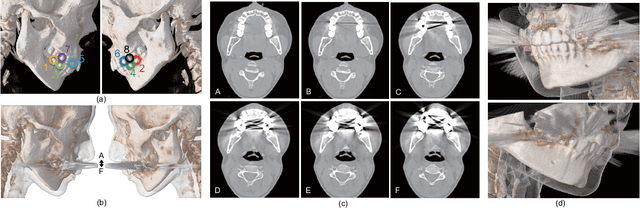

Abstract:The reduction of metal artifacts in computed tomography (CT) images, specifically for strong artifacts generated from multiple metal objects, is a challenging issue in medical imaging research. Although there have been some studies on supervised metal artifact reduction through the learning of synthesized artifacts, it is difficult for simulated artifacts to cover the complexity of the real physical phenomena that may be observed in X-ray propagation. In this paper, we introduce metal artifact reduction methods based on an unsupervised volume-to-volume translation learned from clinical CT images. We construct three-dimensional adversarial nets with a regularized loss function designed for metal artifacts from multiple dental fillings. The results of experiments using 915 CT volumes from real patients demonstrate that the proposed framework has an outstanding capacity to reduce strong artifacts and to recover underlying missing voxels, while preserving the anatomical features of soft tissues and tooth structures from the original images.